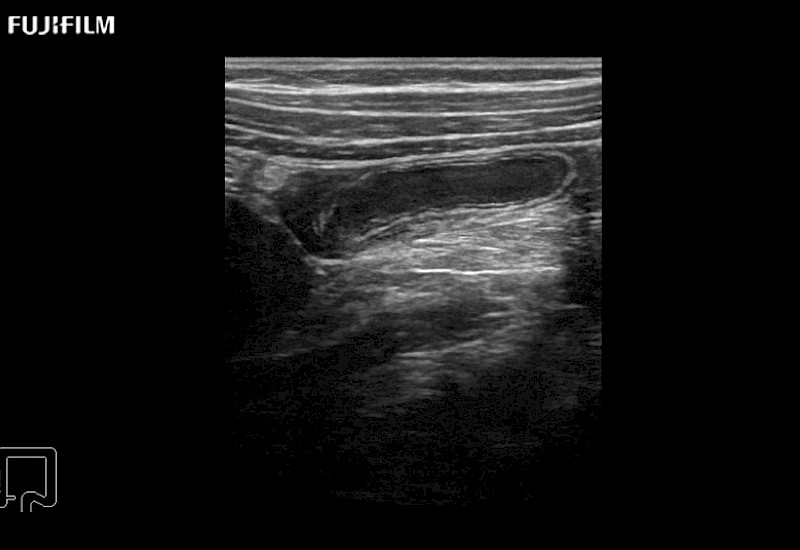

Curved array deep penetration “T” style finger-grip transducer for open surgical procedures.

Curved array 4-way laparoscopic transducer for better visualization of targeted lesions.

Exclusive linear array 4-way laparoscopic transducer for better visualization of targeted lesions.

Exclusive linear array rigid laparoscopic transducer for better visualization of targeted lesions.

Linear array side-fire “T” transducer for open surgical procedures.

Curved array “T” style finger-grip transducer for open surgical procedures.

Curved array deep penetration “I” style finger-grip transducer for open surgical procedures.